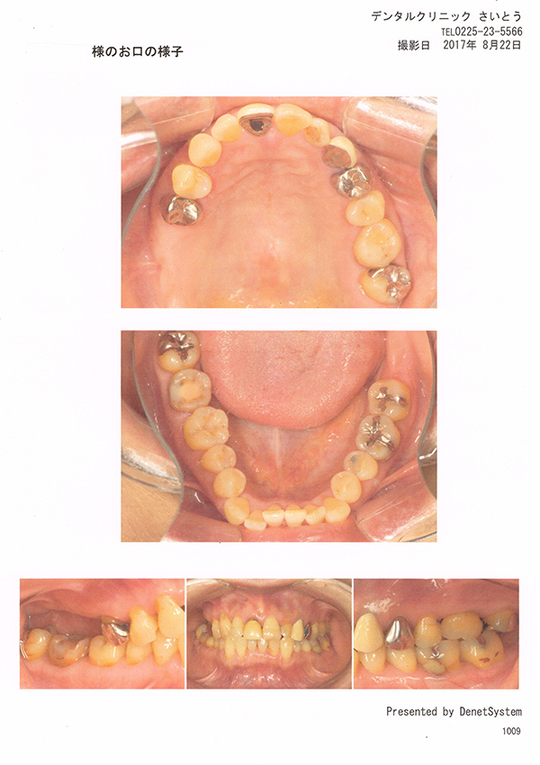

お口の中を5種類のアングルからカメラで撮影します。目視では確認できないところも確認することができます。また、お口の中を患者様ご自身で確認していただくこともできます。